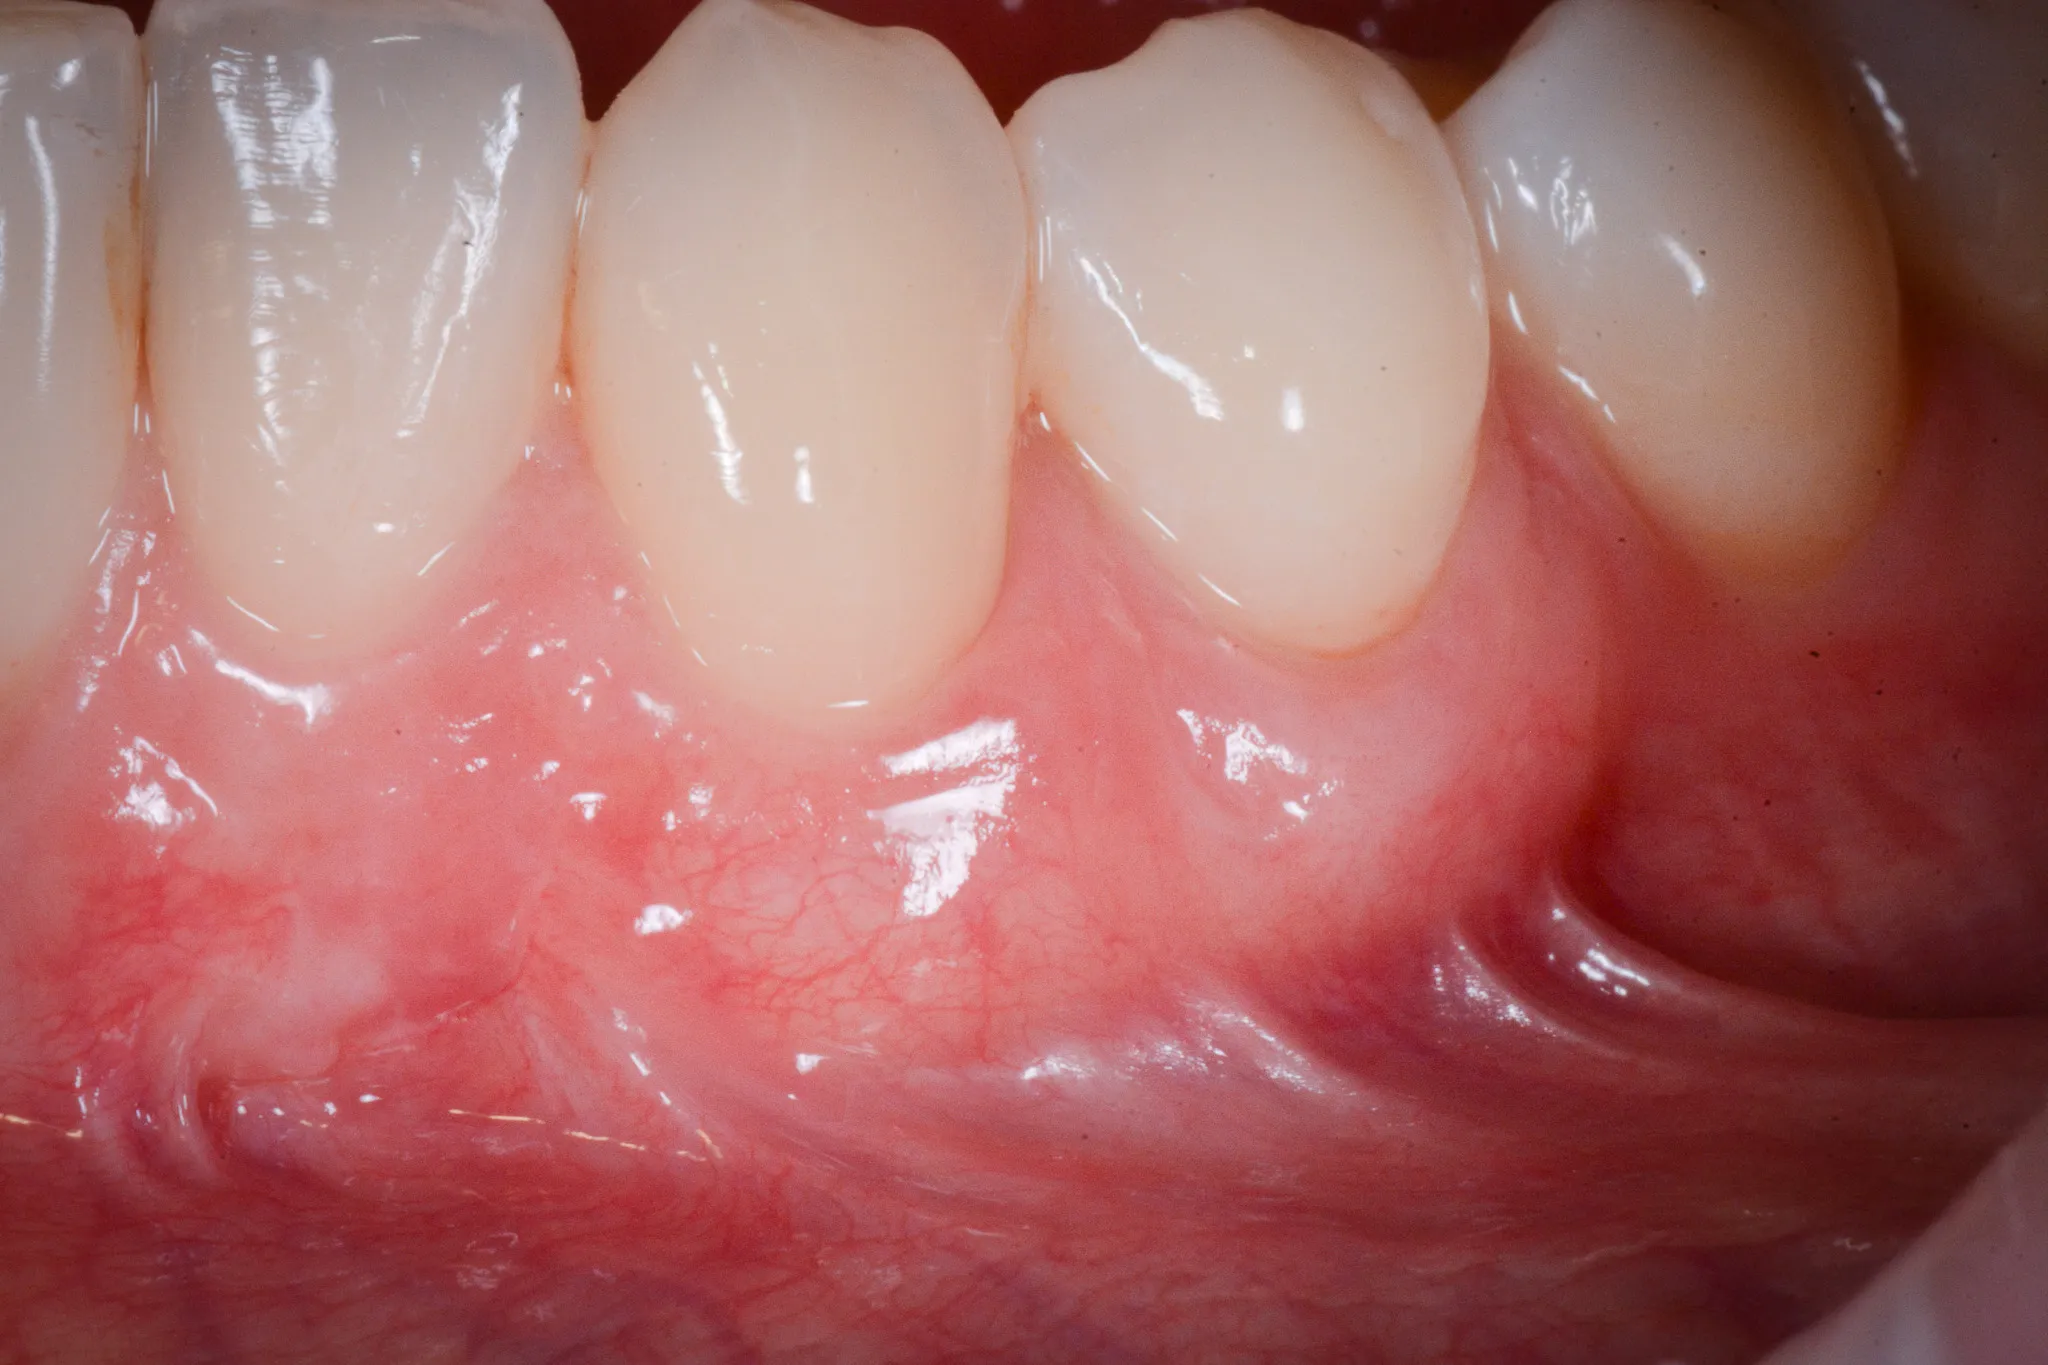

Il tessuto gengivale vero è un tessuto connettivo rivestito da epitelio cheratinizzato (in sostanza, un tessuto più spesso e resistente adeso all’osso sottostante). Quando si ritira, espone la radice del dente — una superficie che non è progettata per stare a contatto con l’ambiente orale. La radice è più porosa dello smalto, più vulnerabile alla carie, più sensibile agli stimoli termici.

Inoltre, a volte la gengiva si assottiglia per vari motivi lasciando spazio da un tessuto più delicato (mucosa orale) che è identico a quello che riveste le guancie e l’interno delle labbra.

Biotipo sottile. Alcune persone hanno gengive sottili per costituzione — una banda stretta di cheratinizzata, un periostio esile, una corticale ossea vestibolare ridotta a un velo. In questi pazienti, anche stimoli minimi possono innescare la recessione.

Il dente che “sembra più lungo” è il segno visivo. Il paziente lo nota allo specchio, oppure lo nota il dentista durante un controllo.

L’altro criterio molto importante è l’ampiezza del tessuto gengivale. Sotto i due millimetri, è consigliabile intervenire.

RT2 — Recessione con perdita di attacco interprossimale, ma inferiore o uguale a quella vestibolare. La prognosi è buona ma la copertura completa non è garantita.

RT3 — Recessione con perdita di attacco interprossimale superiore a quella vestibolare. Il supporto osseo tra i denti è compromesso. La copertura completa è improbabile.

In parole più semplici: se il livello dei tessuti interdentali è ancora conservato, il chirurgo può riportare la gengiva dove era. Se l’osso tra i denti non c’è più, il risultato sarà parziale ma migliorativo.